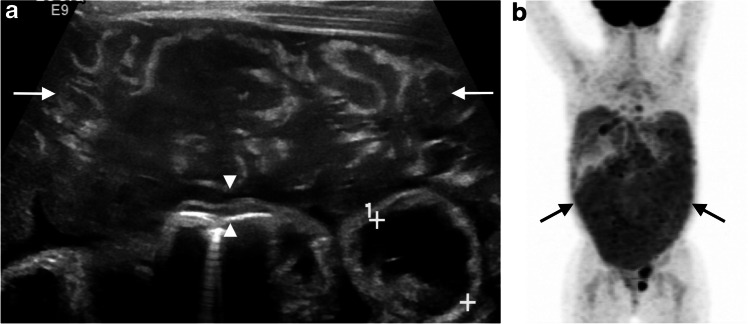

An understanding of normal bowel wall architecture can help refine diagnosis and avoid pitfalls. Documentation of a gut signature, for instance, is considered a confirmatory finding for gastrointestinal duplication cysts, which contain all of the normal bowel layers and share a common muscularis propria with their parent bowel segments. Visualization of bowel wall architecture or its absence can also help correctly identify potential mimics of bowel pathology such as infiltrative or diffuse peritoneal diseases. Plexiform neurofibromas of the mesentery are an uncommon manifestation of neurofibromatosis type 1 that arise along the autonomic nerves accompanying mesenteric vessels or along serosal nerves. Lesions can assume a tubular or multilobular appearance, vaguely resembling collapsed bowel loops, but should be differentiated based upon a targetoid rather than stratified sonographic appearance, with central echogenic collagenous and peripheral hypoechoic myxoid components [12–14]. Peritoneal dissemination of tumor is likewise uncommon in children but can be seen with Burkitt lymphoma, malignant ovarian neoplasms and rhabdomyosarcoma, among others. Peritoneal rhabdomyosarcoma in particular has been observed to produce a cerebriform pattern on US resembling matted or thickened bowel loops but lacking a true gut signature (Fig. 3) [14, 15].

Fig. 3.

Disseminated peritoneal rhabdomyosarcoma, which was initially mistaken for abnormal bowel at an outside institution, in a 3-year-old girl. a Transverse gray-scale US image of the ventral mid-abdomen demonstrates unusual mixed-echogenicity soft tissue with a cerebriform appearance (arrows), vaguely resembling matted bowel loops but lacking the expected multilaminar mural architecture characteristic of subjacent normal bowel (arrowheads; calipers placed by the sonographer measure the approximate luminal diameter of an adjacent bowel loop). b Subsequent positron emission tomography (PET)/CT shows extensive [F-18]2-fluoro-2-deoxyglucose (FDG)-avidity throughout the entire peritoneal cavity (arrows) in the setting of biopsy-proven peritoneal rhabdomyosarcoma